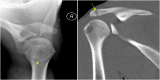

The rotator cuff is a group of four muscles and tendons surrounding the shoulder joint providing it strength and stability. The rotator cuff consists of the subscapularis, supraspinatus, infraspinatus and teres minor. Many shoulder complaints are caused by rotator cuff pathology such as impingement syndrome, tendon tears and other diseases e.g. calcific tendonitis. Diagnosis starts with clinical history and physical examination, after which imaging is often used to help confirm clinical findings depending on the differential diagnosis. The aim of the article is to review the frequently used imaging modalities to assess the rotator cuff and cuff-related disease, specifically focusing on radiography, ultrasonography and magnetic resonance imaging. This article will outline the advantages and disadvantages for each modality and illustrate typical radiological findings of common rotator cuff pathologies.